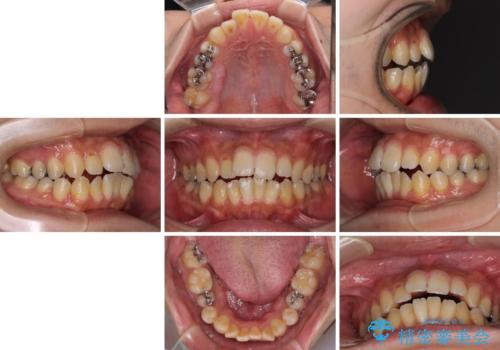

オープンバイトと目立つ銀歯 インビザライン矯正とセラミック修復治療

- 奥歯の目立つ銀歯と上下前歯の叢生と隙間を気にして来院された患者様です。

開咬の治療は、前歯を閉じるように動かすとともに、上下臼歯を圧下(骨内にめり込ませる)させることで進めて行きます。

インビザラインは臼歯の圧下を効果的に行えるため、インビザラインを用いて矯正治療を行うこととしました。

銀歯については、矯正治療により咬合関係を改善し、矯正治療後半に修復治療を行うこととしました。

修復治療後に細かい部分をインビザラインで再度仕上げるプランとしました。